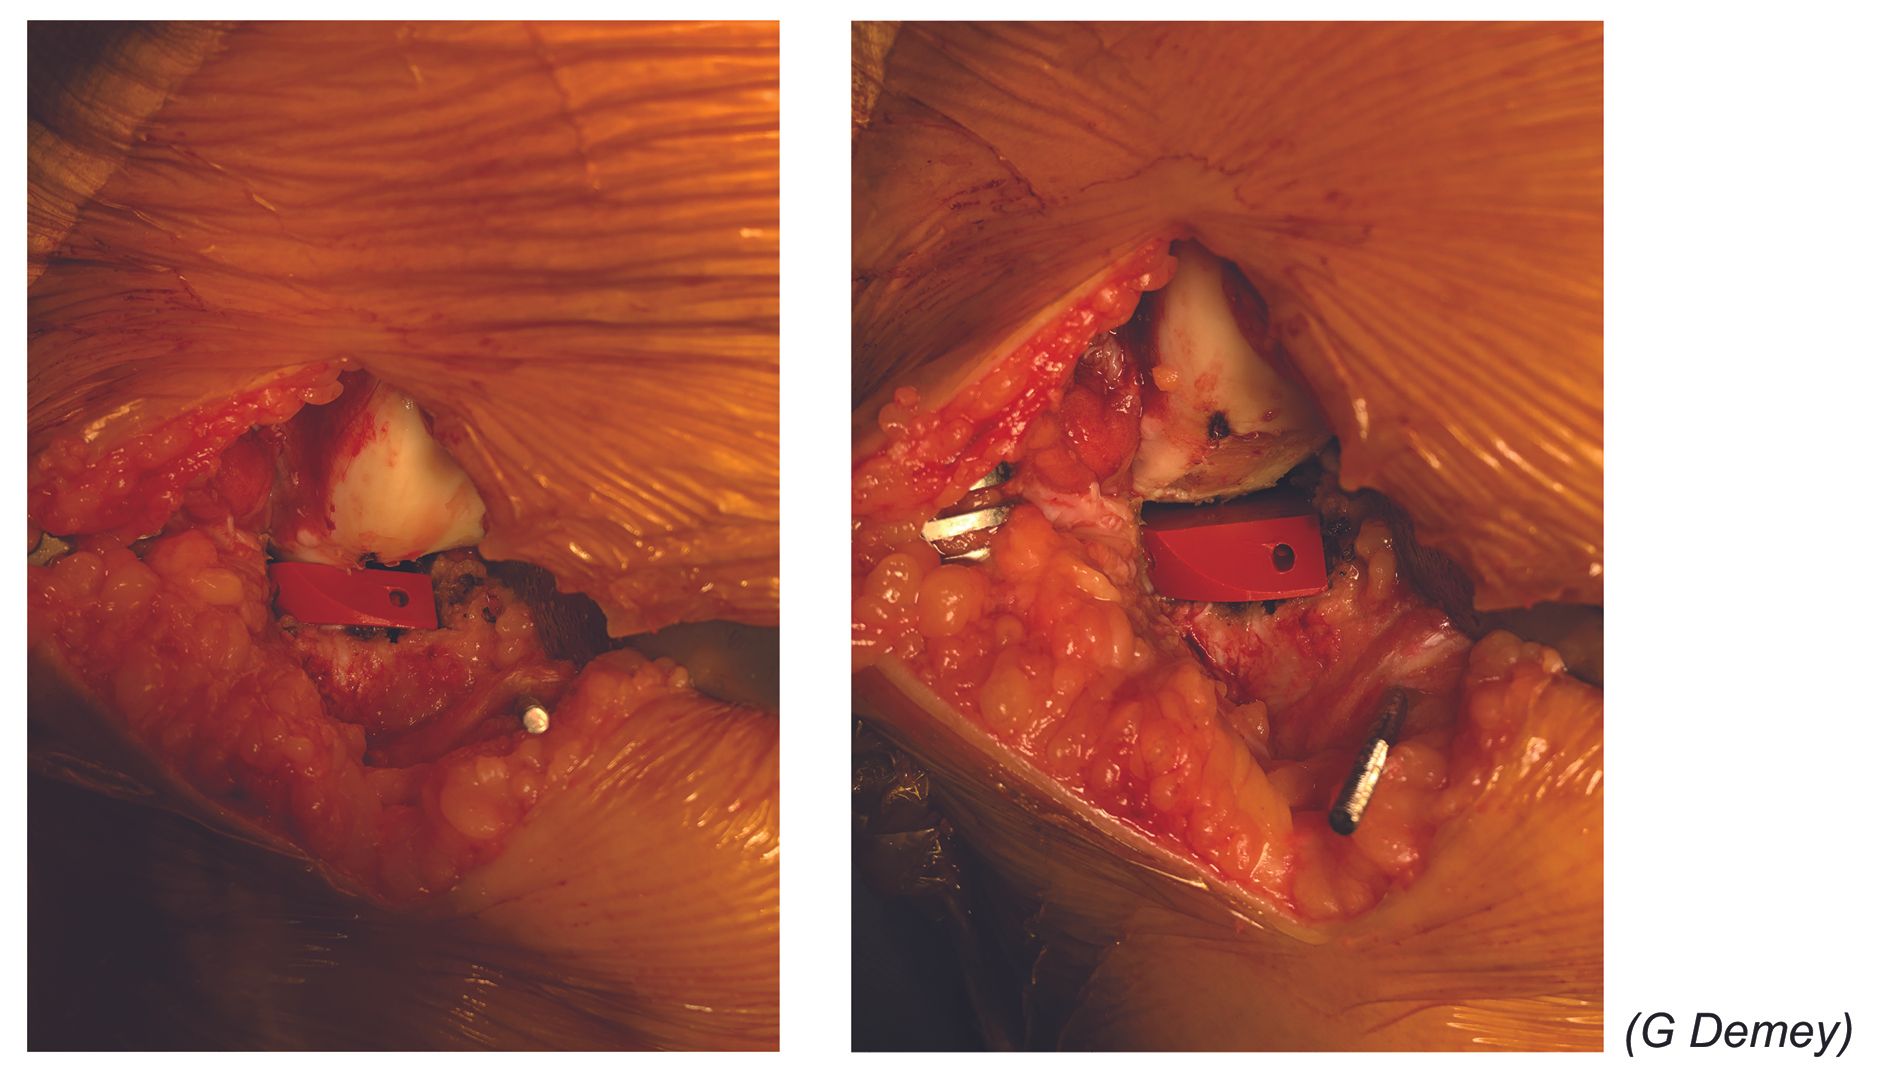

The arthrotomy should be minimal to avoid damaging the trochlear cartilage, medial meniscus or cruciate ligaments (which will have been checked at the start of the procedure). It is important to leave sufficient tissue over the patellar side to be able to close the arthrotomy, by routinely retaining the Hoffa fat pad pediculated to the anterolateral meniscocapsular structures (Fig. 7). Osteophytes should be removed from the notch, but any osteophytes on the lateral condyle should be kept since they are commonly used to support the femoral head.

Positioning the femoral guide and femoral cuts

For femur, in the frontal plane, the implant should be positioned very laterally, resting on the condylar osteophytes which should have been preserved specifically for this purpose (Fig. 12). Place the knee in flexion to check for lateral rotation of the implant (Fig. 13), in order to avoid any camber in extension i.e. frontal slippage of the implant onto its upslope via the screw-home mechanism: this lateral tibia-on-femur rotation occurs in the final 20 degrees of knee extension and allows the two cruciate ligaments to lock the knee.

Use an appropriate size femoral implant (Fig. 14) and in particular avoid an oversized component (leave a margin of 2mm from the anterior cartilaginous edge of the distal cut) to avoid patellar impingement, which can cause pain. With both the trial and final components, check that femur is centred on tibia and that there is no impingement on the spines or any overhang of the tibial plateau (Fig. 15). The key to good long-term results is avoiding overcorrection. The polyethylene component should therefore be thin, with a laxity ‘safety margin’ in varus.